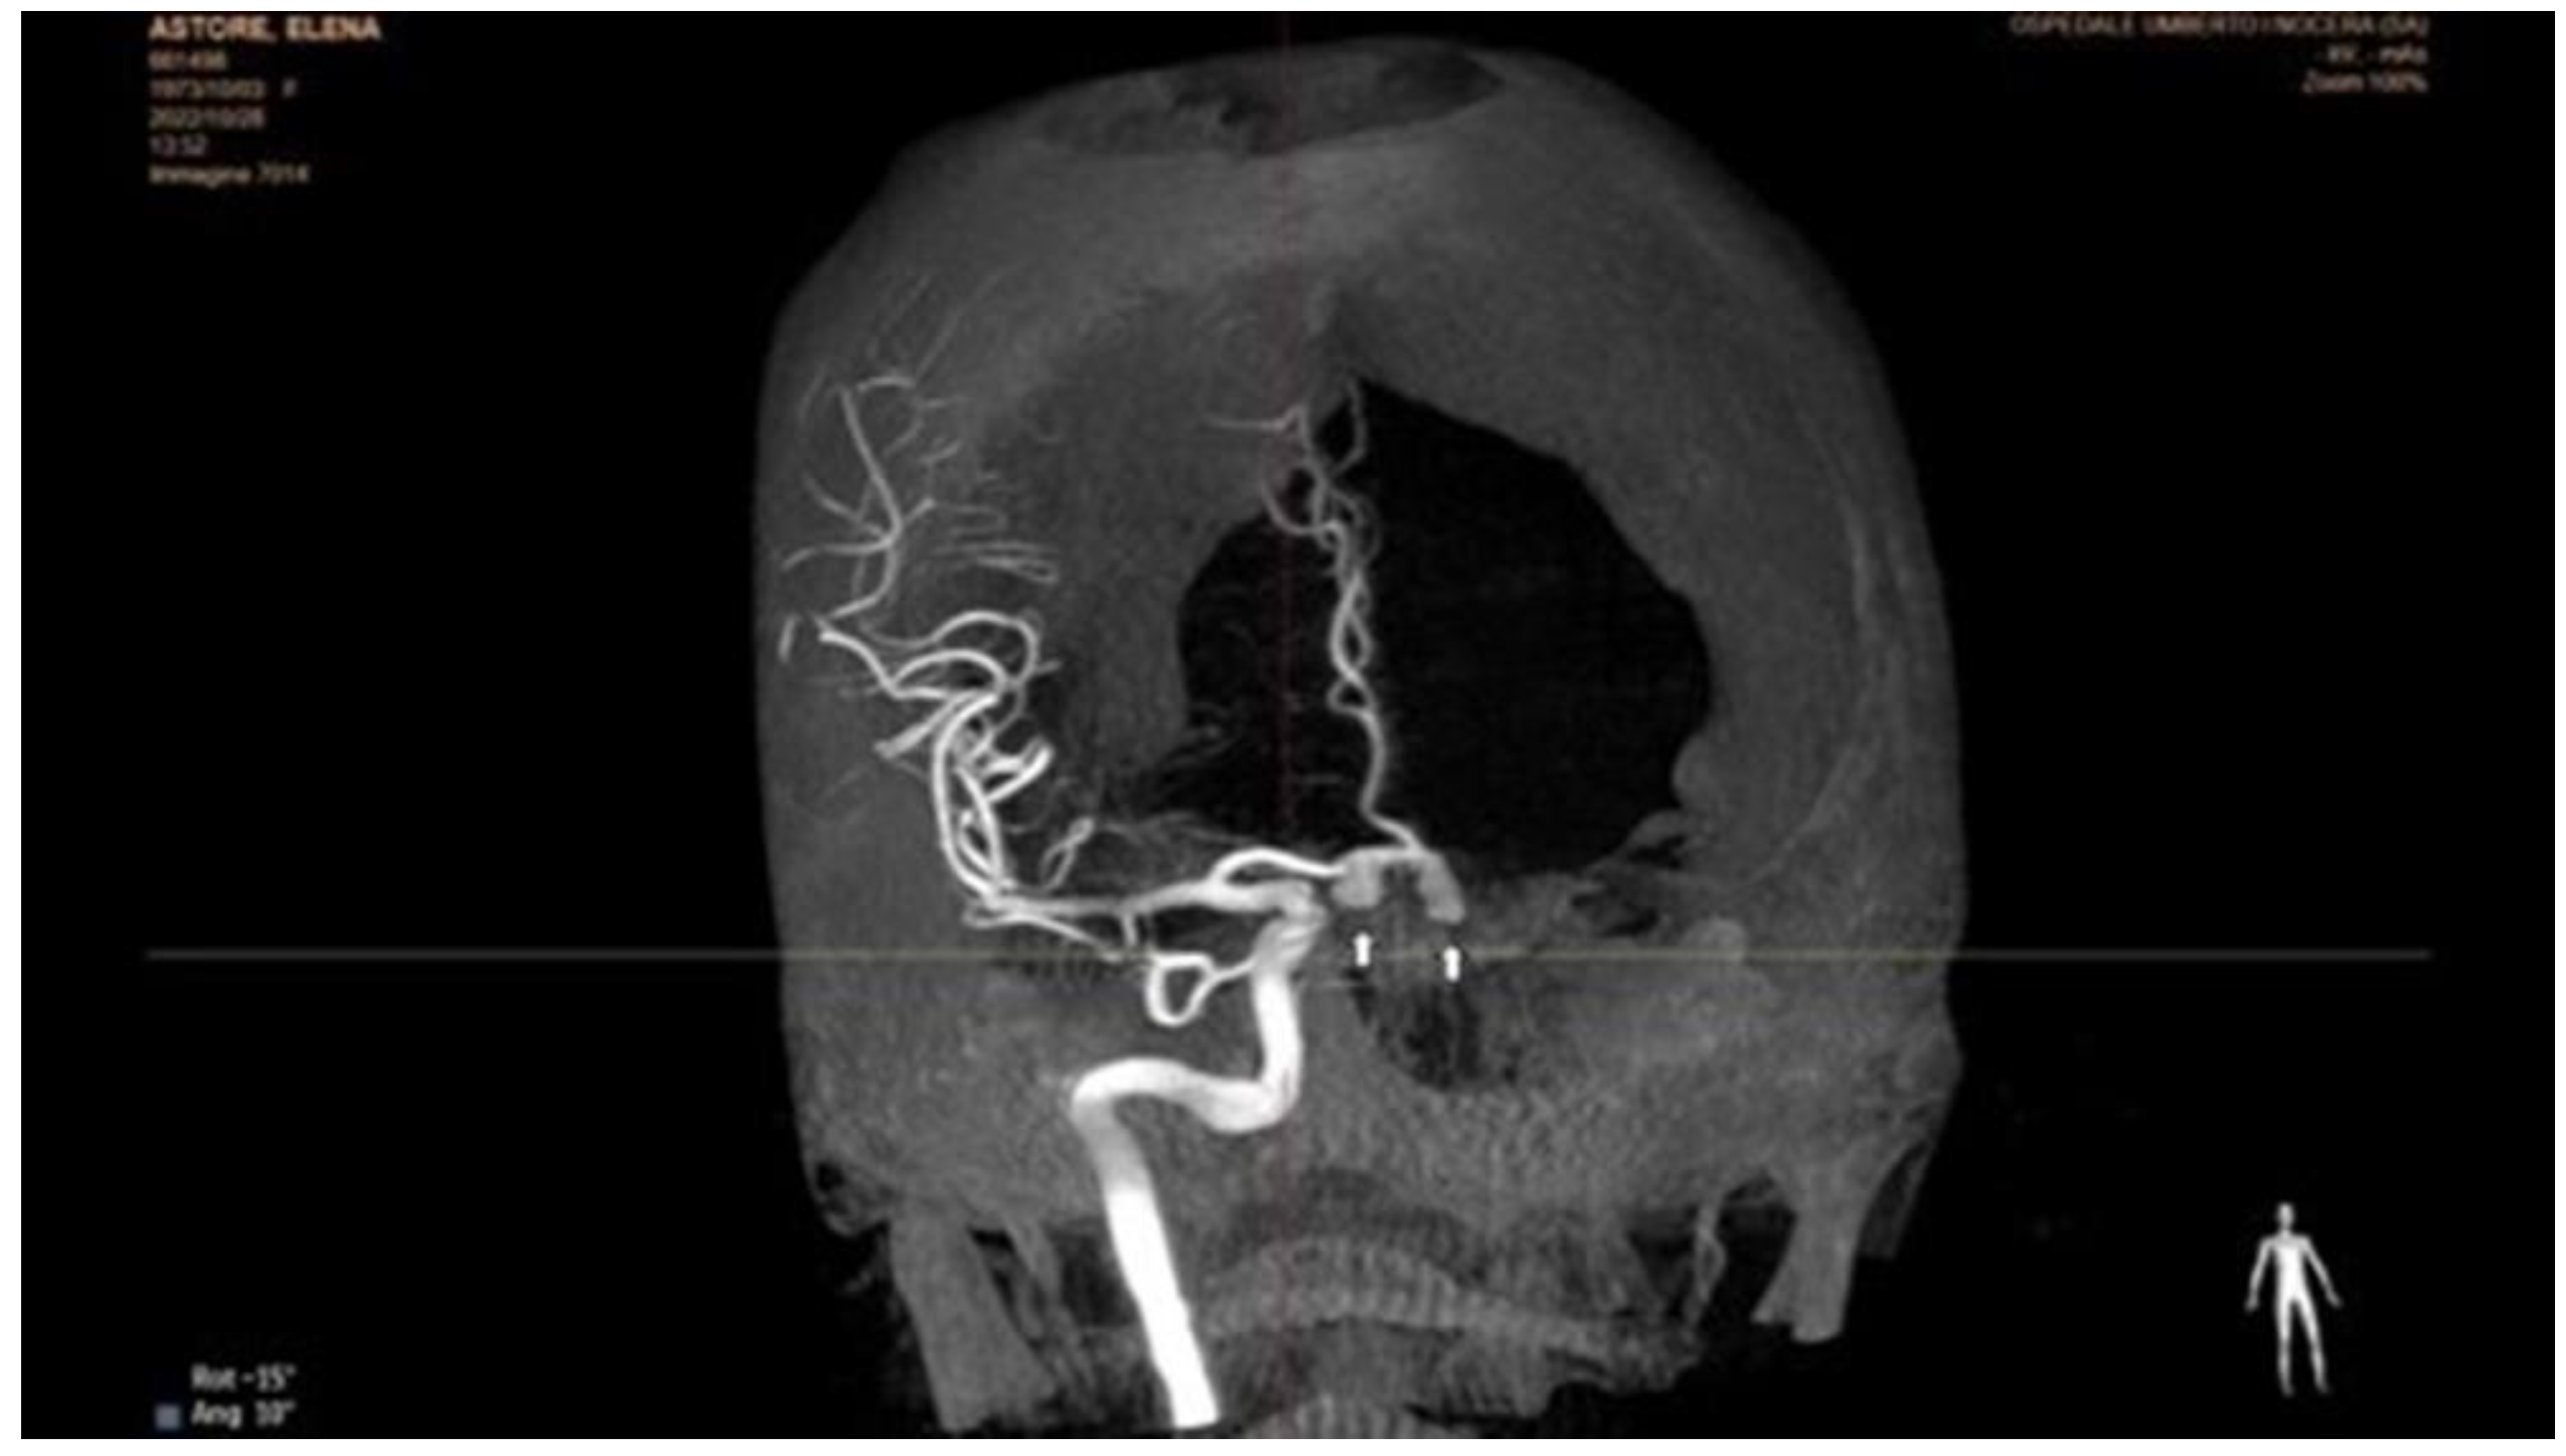

5.1. Angiography

- Prasad, M.; Tweet, M.S.; Hayes, S.N.; Leng, S.; Liang, J.J.; Eleid, M.F.; Gulati, R.; Vrtiska, T.J. Prevalence of extracoronary vascular ab-normalities and fibromuscular dysplasia in patients with spontaneous coronary artery dissection. Am. J. Cardiol. 2015, 115, 16727. [Google Scholar] [CrossRef]

- Tweet, M.S.; Gulati, R.; Williamson, E.E.; Vrtiska, T.J.; Hayes, S.N. Multimodality Imaging for Spontaneous Coronary Artery Dissection in Women. JACC Cardiovasc. Imaging 2016, 9, 436–450. [Google Scholar] [CrossRef]